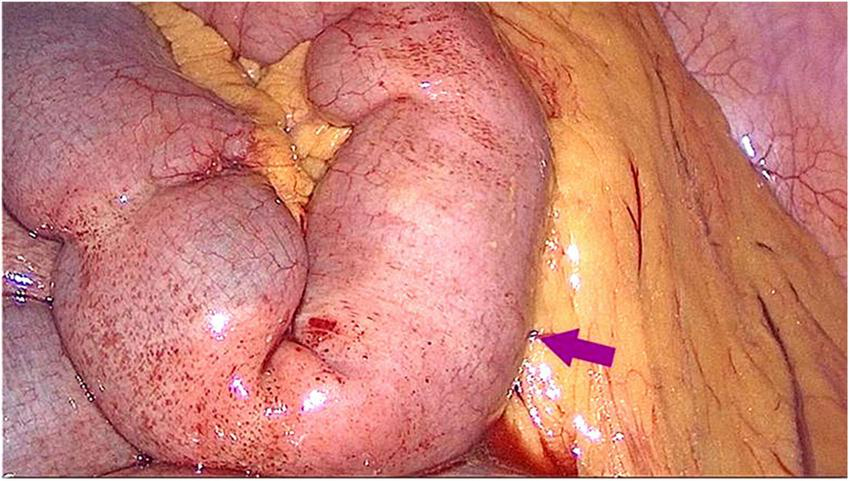

A 45-year-old female patient presented to the emergency department with a 5-day history of abdominal pain, nausea, and vomiting. The abdominal pain was colic-like, and abdominal distension was present; bowel movements and flatus were absent. The patient had a history of two cesarean sections and denied any previous GI issues. However, she reported the consumption of a large quantity of pears 2 days before the onset of symptoms. Physical examination revealed abdominal distension and tenderness upon palpation without rebound tenderness or muscular rigidity. Bowel sounds were diminished. Laboratory investigations revealed no significant abnormalities. A computed tomography (CT) scan showed several dilated small-bowel loops with fluid in the abdomen and a transition point in the right lower abdomen (Figure 1). The patient was diagnosed with SBO, and the possibility of a neoplasm was also considered. The patient was subsequently admitted for conservative management, which included fasting, intravenous fluid administration, antibiotics, and nasogastric tube decompression. Despite 28 h of conservative management, the patient’s symptoms persisted. Thus, we counseled the patient and the family in detail about the risks of continuing non-operative treatment—namely, bowel perforation, peritonitis, intestinal ischemia, surgical delay, symptom progression, and psychological stress while also explaining the potential risks and benefits of laparoscopic exploration. After careful consideration, the patient and family elected to proceed with laparoscopic surgery. No adhesions were observed during the surgical procedure, and a foreign body obstructing the intestinal canal was discovered approximately 60 cm from the ileocecal region. This obstruction resulted in significant dilation and fluid accumulation in the proximal intestinal canal, and the distal section collapsed (Figure 2). A 4-cm incision was made in the abdomen to access the obstruction site, and a longitudinal enterotomy was performed to extract the foreign body (Figure 3). The foreign body was identified as a bezoar measuring approximately 30 mm × 30 mm; the specimen fragmented into multiple pieces during extraction (Figure 4A). The bezoar was subsequently analyzed, revealing that it comprised undigested pear material (Figure 4B). The intestinal incisions were closed transversely, and the abdominal incisions were closed in a layered manner. The patient experienced an uneventful recovery and was discharged on the fifth postoperative day with dietary modification instructions to prevent future occurrences of gastrolithiasis. The patient showed no signs of recurrent SBO or surgery-related complications at the 3-month follow-up.

Figure 2. Laparoscopic examination revealed a columnar foreign body impacted within the small intestinal lumen approximately 60 cm from the ileocecal valve.